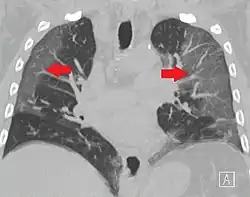

W badaniu 1099 chińskich pacjentów za pomocą tomografii komputerowej stwierdzono zmiany w płucach typu mlecznej szyby w 56% przypadków. Zmian w badaniu radiologicznym nie wykazano u 17,9% pacjentów z łagodną postacią choroby oraz u 2,9% pacjentów z ciężką postacią choroby. Limfopenia była obecna u 83,2% przyjętych pacjentów. 5% pacjentów zostało przyjętych na oddziały intensywnej terapii, 2,3% wymagało mechanicznego wspomagania wentylacji płuc, a 1,4% zmarło[39]. Według zespołu badawczego Bernheima obustronne i obwodowe zacienienia w płucach typu mlecznej szyby są najczęstszymi objawami widocznymi na skanach tomografii komputerowej. Konsolidacje miąższu płucnego, liniowe zacienienia płuc oraz objaw odwróconego halo to inne typowe symptomy widoczne w obrazowaniu radiologicznym. Początkowo zmiany są widoczne w jednym płucu, jednak – wraz z rozwojem choroby – u 88% pacjentów stają się obecne w obu płucach[40]. Dzieci zdają się przechodzić chorobę lepiej niż dorośli i występują u nich łagodniejsze objawy, jednak brakuje wciąż danych, aby stwierdzić to jednoznacznie[41].

Zmiany w diagnostyce obrazowej u pacjentów obejmują najczęściej[47][50][55]:

- obustronne i obwodowe zacienienia w płucach typu „mlecznej szyby”

- niejednolite konsolidacje miąższu płucnego

- liniowe zacienienia w płucach

- objawy odwróconego halo

- predylekcję do występowania zmian w tylnych segmentach lub płatach dolnych